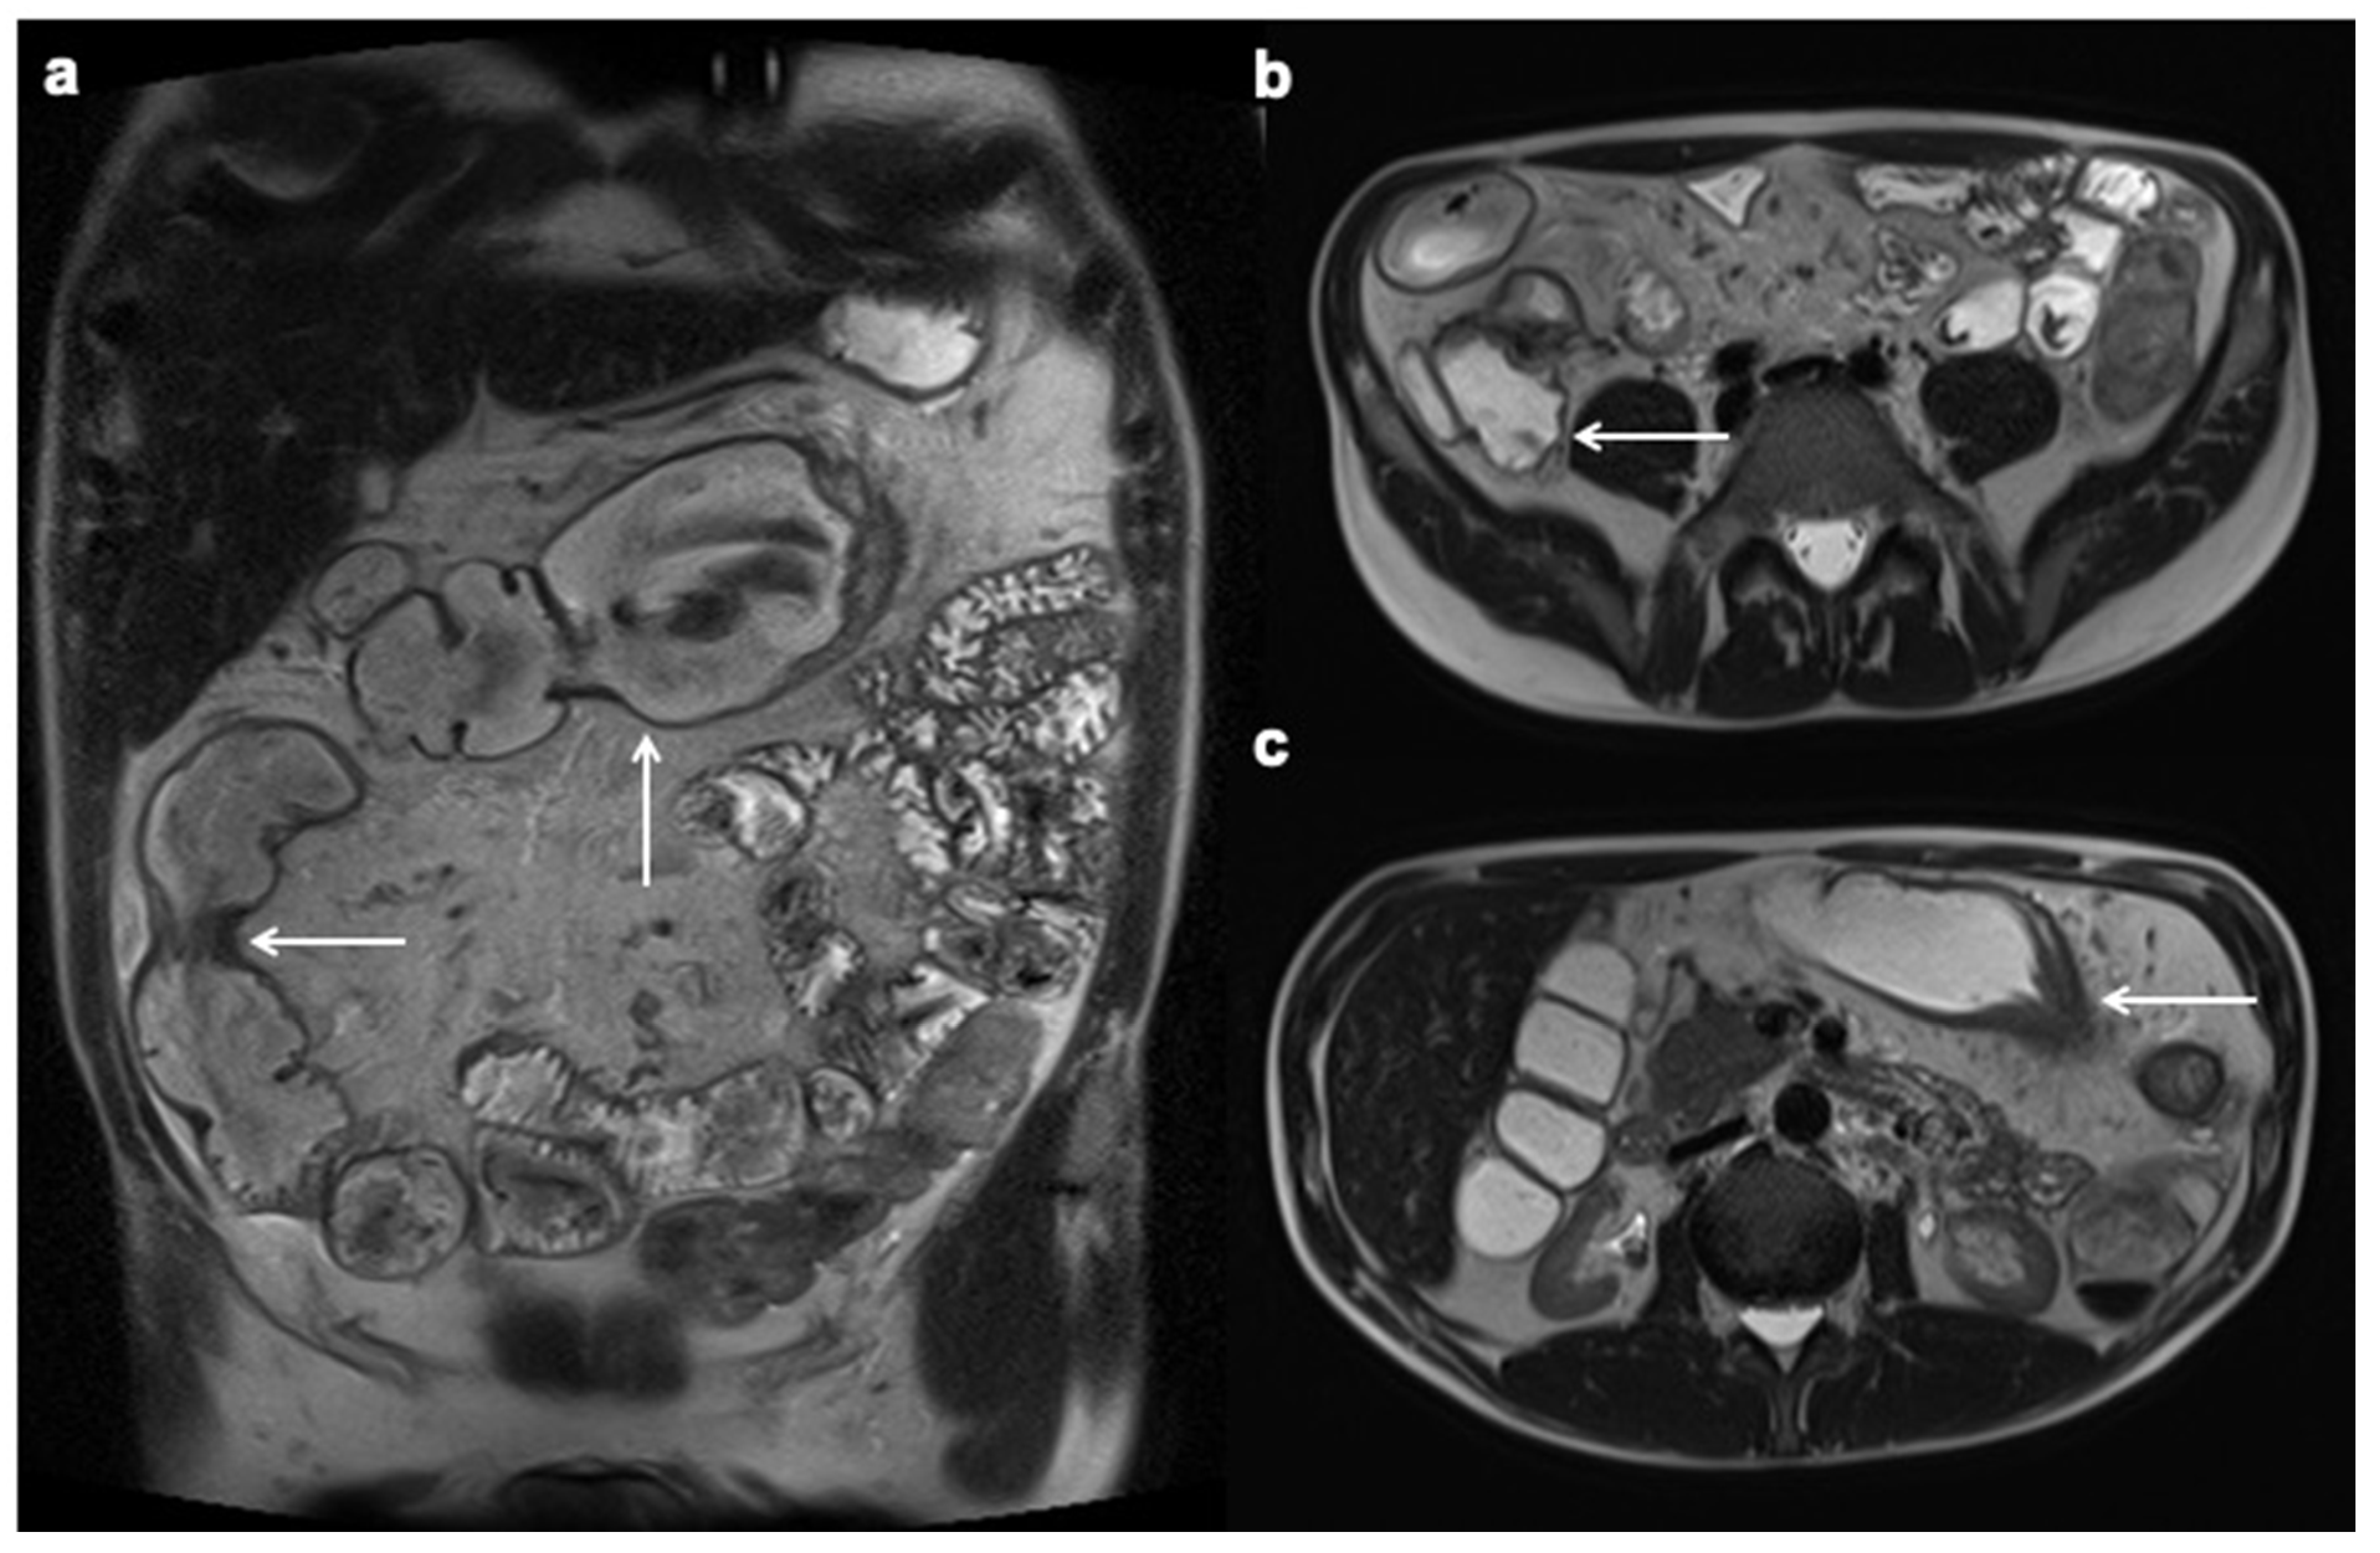

- Dohan, A.; Taylor, S.; Hoeffel, C.; Barret, M.; Allez, M.; Dautry, R.; Zappa, M.; Savoye-Collet, C.; Dray, X.; Boudiaf, M.; et al. Diffusion-weighted MRI in Crohn’s disease: Current status and recommendations. J. Magn. Reson. Imaging 2016, 44, 1381–1396. [Google Scholar] [CrossRef] [Green Version]

- Kim, K.J.; Lee, Y.; Park, S.H. Diffusion-weighted MR enterography for evaluating Crohn’s disease: How does it add diagnostically to conventional MR enter-ography? Inflamm. Bowel Dis. 2015, 21, 101–109. [Google Scholar] [CrossRef]

- Seo, N.; Park, S.H.; Kim, K.-J.; Kang, B.-K.; Lee, Y.; Yang, S.-K.; Ye, B.D.; Park, S.H.; Kim, S.Y.; Baek, S.; et al. MR Enterography for the Evaluation of Small-Bowel Inflammation in Crohn Disease by Using Diffusion-weighted Imaging without Intravenous Contrast Material: A Prospective Noninferiority Study. Radiology 2016, 278, 762–772. [Google Scholar] [CrossRef]

- Morani, A.C.; Smith, E.A.; Ganeshan, D.; Dillman, J.R. Diffusion-Weighted MRI in Pediatric Inflammatory Bowel Disease. Am. J. Roentgenol. 2015, 204, 1269–1277. [Google Scholar] [CrossRef]

- Park, S.H. DWI at MR Enterography for Evaluating Bowel Inflammation in Crohn Disease. Am. J. Roentgenol. 2016, 207, 40–48. [Google Scholar] [CrossRef]